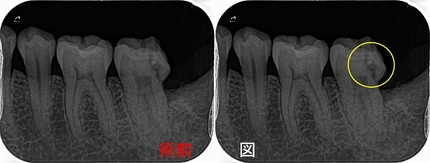

診査すると神経は死んでおり、CTでも根尖病変が確認できる。

2026 EEdental TAY (2).jpg

樋状根でした。

*ML根は途中で石灰化をしており穿通できず、たぶん早い時期に治療をスタートしていれば穿通出来たかも!?